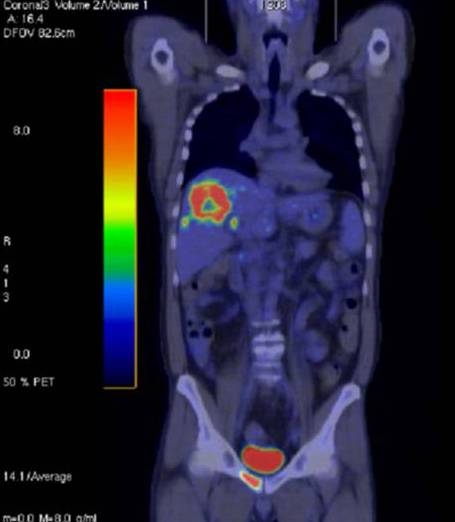

14.1.1.9. Hybrid imaging modalities, PET/CT

If the Positron Emission Tomography and Multidetector CT images are performed exactly in the same set and will be superprojected, a quite accurate localisation of metabolically active, pathological liver lesions can be managed. The administrated PET radiopharmacon (fluorodeoxyglucose, FDG) gets stuck in the hypermetabolic (glucose uptaking) cells marking accurately these hypermetabolic areas. (Figure 11)

Figure 11: PET/CT of the liver, HCC

Concerning the liver in the oncologic field, PET/CT technique plays a very important role in the detection of metastases.